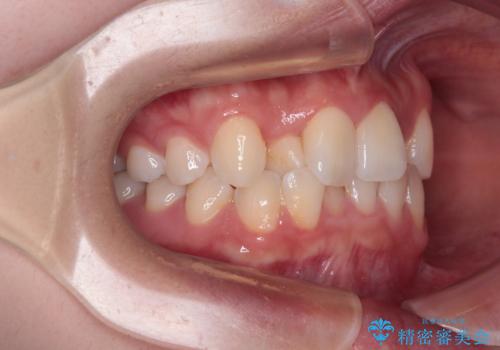

前歯のクロスバイト 裏側に隠れた歯をワイヤー装置で短期間治療

- 上顎前歯のクロスバイトを気にして来院された患者様です。

ワイヤー矯正でもマウスピース矯正でも対応可能でしたが、マウスピースによる自己管理に一切の自信がないとのことで、ワイヤー装置にて矯正治療を行うこととしました。